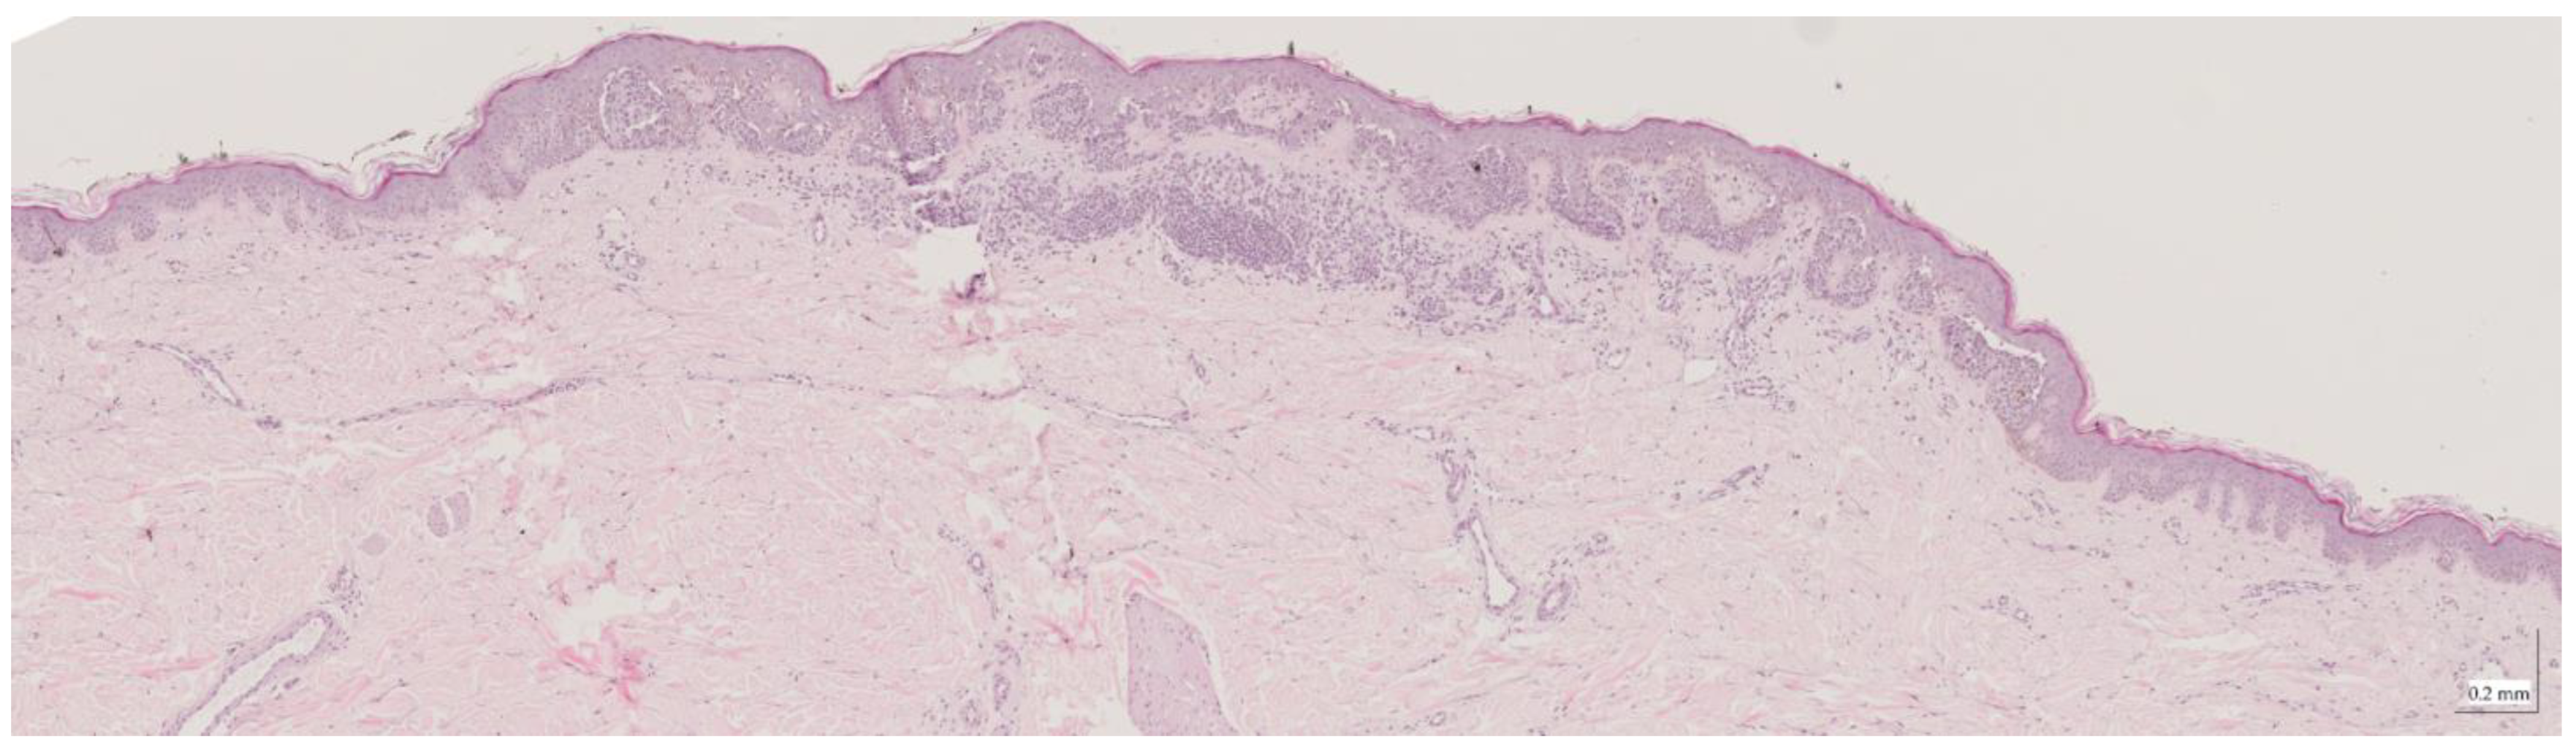

| Compound nevus (CN) Case 1 | Localization: right dorsal |

![]() | ![]() |

| Compound nevus (CN) Case 2 | Localization: right posterior thigh |